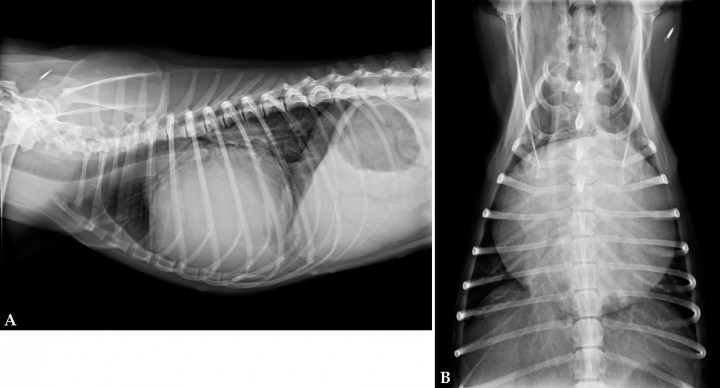

Se presenta en la consulta una perra hembra esterilizada mestiza de Beagle de 11 años de edad y 10 kilos de peso, con historia clínica de tos desde hace tres semanas y un episodio de pérdida del tono postural con relajación de esfínteres. En la exploración física se observan mucosas pálidas, tiempo de relleno capilar aumentado (3 segundos), un soplo holosistólico III/IV de máxima intensidad en el ápex izquierdo con los tonos cardiacos ligeramente atenuados, leve aumento de la frecuencia respiratoria (40 rpm), frecuencia cardiaca de 160 lpm y pulso eucinético. Se realiza una analítica sanguínea completa en la que, en la bioquímica sérica, se aprecia una ligera hipoproteinemia (4,9 g/dl con valores de referencia de 5,0-7,2 g/dl), una hipoalbuminemia (2,2 g/dl con valores de referencia 2,6-4,0 g/dl) y un ligero aumento de la fosfatasa alcalina (94 U/l, con valores de referencia 13,0-83 U/l). No se observan alteraciones en el hemograma ni en las pruebas de coagulación (PT y aPTT). Se realizan radiografías de tórax en proyecciones ortogonales (lateral y ventrodorsal) (Fig. 1)

<p>Radiografías de tórax de un paciente que se presenta con episodio de pérdida del tono postural con relajación de esfínteres. (<strong>A</strong>) Proyección lateral derecha. (<strong>B</strong>) Proyección ventrodorsal.</p>

Radiografías de tórax de un paciente que se presenta con episodio de pérdida del tono postural con relajación de esfínteres. (A) Proyección lateral derecha. (B) Proyección ventrodorsal.